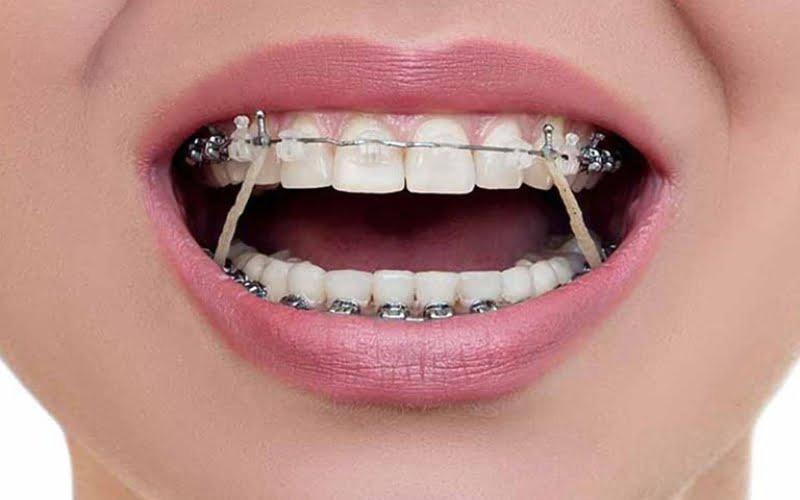

Dây chun liên hàm có độ đàn hồi cao và được sử dụng phổ biến trong điều trị chỉnh nha

Chun liên hàm là một chiếc vòng cao su có độ đàn hồi cao, được gắn từ hàm trên xuống hàm dưới nhằm tạo ra lực kéo ổn định, giúp răng di chuyển về đúng vị trí mong muốn. Vị trí gắn dây chun có thể là các móc có sẵn trên mắc cài hoặc gắn vào minivis để điều chỉnh răng.

Khí cụ được móc vào mắc cài ở hàm trên và hàm dưới sẽ giúp căn chỉnh lại khớp. Lúc này, hai đầu dây chun sẽ tạo ra một áp lực lớn nhằm kéo răng về đúng vị trí. Dùng chun liên hàm trong chỉnh nha giúp bạn rút ngắn thời gian niềng răng nhưng cần sử dụng theo chỉ định của bác sĩ để đảm bảo hàm răng đều đẹp hơn.